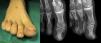

The differential diagnosis comprehends a range of conditions associated with onychodystrophy, such as onychomycosis, plantar warts or ingrown toenails. The mere suspicion of a tumour as the cause of ungual abnormalities can streamline the diagnosis and treatment. The diagnosis is made by plain radiography with two orthogonal projections, which allows visualization of the bony overgrowth (Fig. 1).